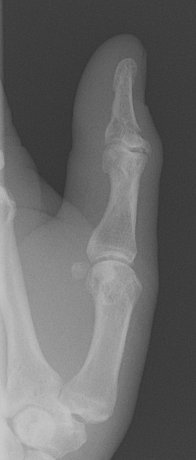

Return to Phalangeal Fracture (Hand)